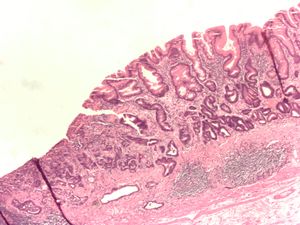

Poor to moderately differentiated adenocarcinoma of the stomach. H&E stain.

Adenocarcinoma of the stomach and intestinal metaplasia. H&E stain.